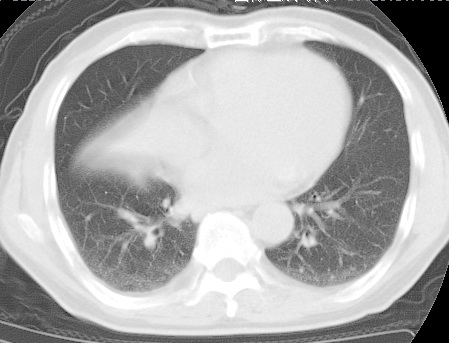

标题: CT24032:男65岁,咳嗽,吸烟20余年,无发热,咳痰 [打印本页]

标题: CT24032:男65岁,咳嗽,吸烟20余年,无发热,咳痰

考虑右肺中叶不张,请大家发表意见

右肺中叶不张、肺门轮廓增大,占位不除外;建议增强,必要时支气管镜详查。

右肺中叶支气管闭塞,中叶肺不张,右侧肺门见肿块影。中心型肺癌的可能大。建议支气管镜检查。

右中叶体积明显缩小,且其支气管未显示,先考虑:中心型肺癌班右中叶肺不张。

建议:支气管镜检查。

考虑右肺中叶中央型肺癌并右肺中叶肺不张;建议:行纤支镜检查。

右肺门旁类圆形肿块影,右肺中叶不张,建议纤支镜检查。

1右肺门旁类圆形肿块影,右肺中叶不张,建议纤支镜检查

2右侧胸膜增厚,右侧叶间胸膜区钙化

3右肺下叶小囊状透亮影考虑肺气肿

平片就可以诊断右肺中叶不张,做CT就是要找原因!中叶支气管开口不清,建议支气管镜检查。